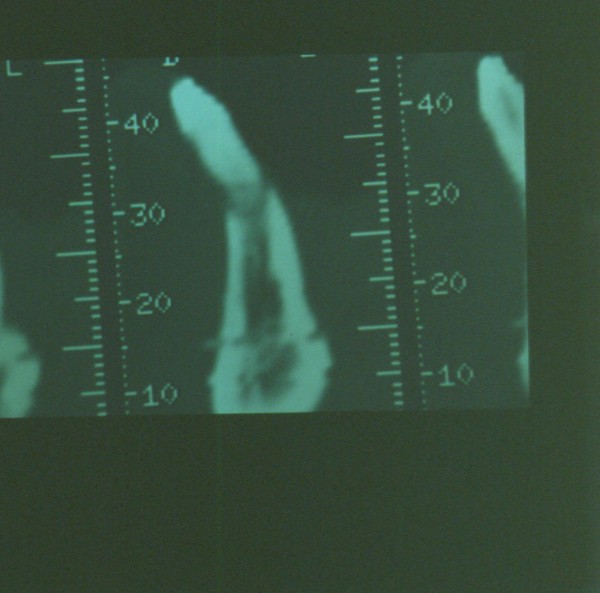

Todos estos parámetros fueron constatados por la toma de una imagen DIGORA (DIAPO 2), con una precisión tal , que corroboraba la visión de la claridad del caso

DIAPO 2